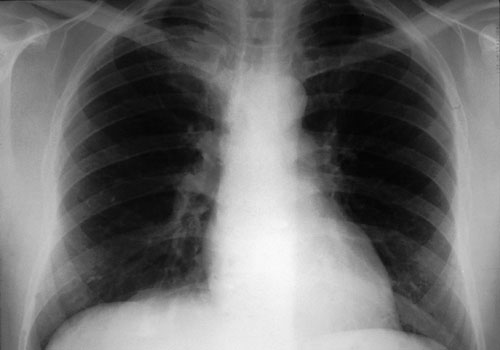

2: Chest x-ray in Streptococcus pneumoniae pneumonia

Chest x-ray is the cardinal investigation in community-acquired pneumonia, but may occasionally be misleading.

At presentation: A 47-year-old smoker presented after just a few hours of rigors and productive cough. Despite clinical signs of right upper zone consolidation, chest x-ray showed only minor abnormalities. Empirical therapy for community-acquired pneumonia was begun.

12 hours later: Chest x-ray showed consolidation in the right upper lobe consistent with the earlier clinical signs. S. pneumoniae was isolated from blood cultures. The patient recovered fully. (X-rays courtesy of Dr Bryan Speed, Fairfield Hospital Historical Collection, Melbourne, VIC.)